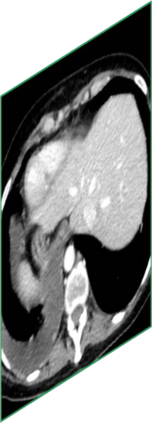

Due to the constraints of the imaging device and high cost in operation time, computer tomography (CT) scans are usually acquired with low intra-slice resolution. Improving the intra-slice resolution is beneficial to the disease diagnosis for both human experts and computer-aided systems. To this end, this paper builds a novel medical slice synthesis to increase the between-slice resolution. Considering that the ground-truth intermediate medical slices are always absent in clinical practice, we introduce the incremental cross-view mutual distillation strategy to accomplish this task in the self-supervised learning manner. Specifically, we model this problem from three different views: slice-wise interpolation from axial view and pixel-wise interpolation from coronal and sagittal views. Under this circumstance, the models learned from different views can distill valuable knowledge to guide the learning processes of each other. We can repeat this process to make the models synthesize intermediate slice data with increasing inter-slice resolution. To demonstrate the effectiveness of the proposed approach, we conduct comprehensive experiments on a large-scale CT dataset. Quantitative and qualitative comparison results show that our method outperforms state-of-the-art algorithms by clear margins.

翻译:由于成像装置的限制和操作时间成本高,计算机断层扫描通常以低切片分辨率获得。改进切片内分解法有利于人类专家和计算机辅助系统进行疾病诊断。为此,本文件制作了新的医疗切片合成法,以增加解片之间的解析。考虑到临床实践中总是没有地面真相中间医疗切片,我们采用渐进的跨视图相互蒸馏战略,以自我监督的学习方式完成这项任务。具体地说,我们用三种不同的观点来模拟这一问题:从轴视中切片间解法和从正弦和方位角度对等离子间解法。在此情况下,从不同观点中学习的模型可以提取宝贵的知识,用以指导彼此的学习过程。我们可以重复这一过程,使模型合成中间切片数据,同时增加分裂分辨率。为了证明拟议方法的有效性,我们在大规模CT数据集上进行了全面的实验。通过清晰的定量和定性的算法比较结果显示,我们的方法将超越了一种方法。